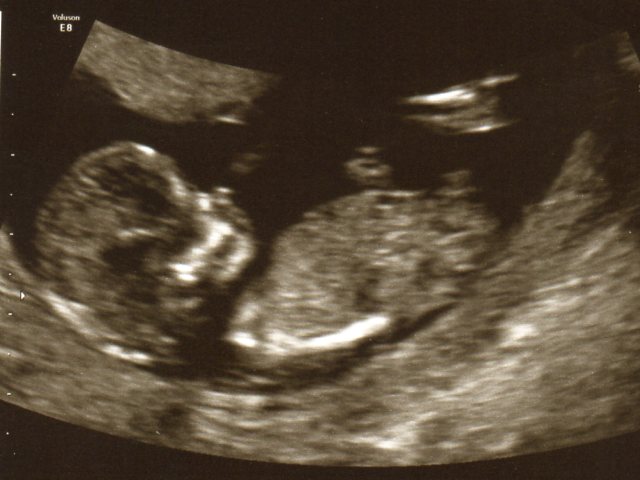

Compared to these 12 weeks + 5 Days pictures everyone has said BOY but looking more like a girl to me in 21 weeks.

Attachment 13164